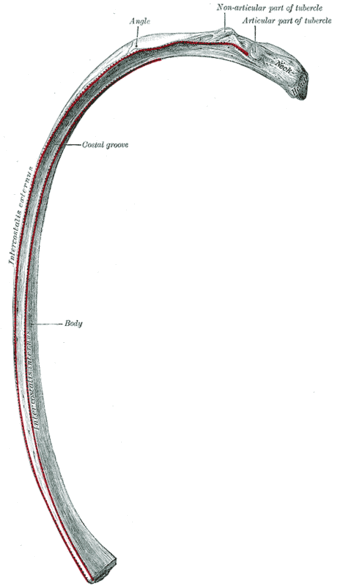

أجزاء الضلع

- رأس الضلع : وهو نهاية الضلع القريبة إلى العمود الفقري.

- المفصل الضلعي الفقري : وهو مكان تمفصل رأس الضلع مع الفقرة الصدرية.

- عنق الضلع : وهو جزء الضلع المسطح الذي يمتد على جانب جسم الإنسان.

- الحديبة الضلعية : وهو نتوء في السطح الخلفي للضلع.

- زاوية الضلع : وهو المكان المنحني في الضلع.

- الثلم الضلعي : وهو شق بين السطح الداخلي للضلع وبين والحافة السفلى للضلع.